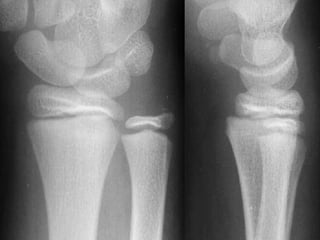

DIAGNOSTICO Clínico Radiológico  2 proyecciones o mas

ESTUDIOS RADIOGRAFICOS SIMPLES Corroboran la presencia de Fx. Permiten darse cuenta de la lesión de partes blandas La localización de la Fx. Tipo de trazos de la Fx. Numero de fragmentos El desplazamiento La presencia o ausencia de una patología

LOCALIZACION Diafisiaria Metafisiaria Epifisiaria Intraarticular Fractura-luxación